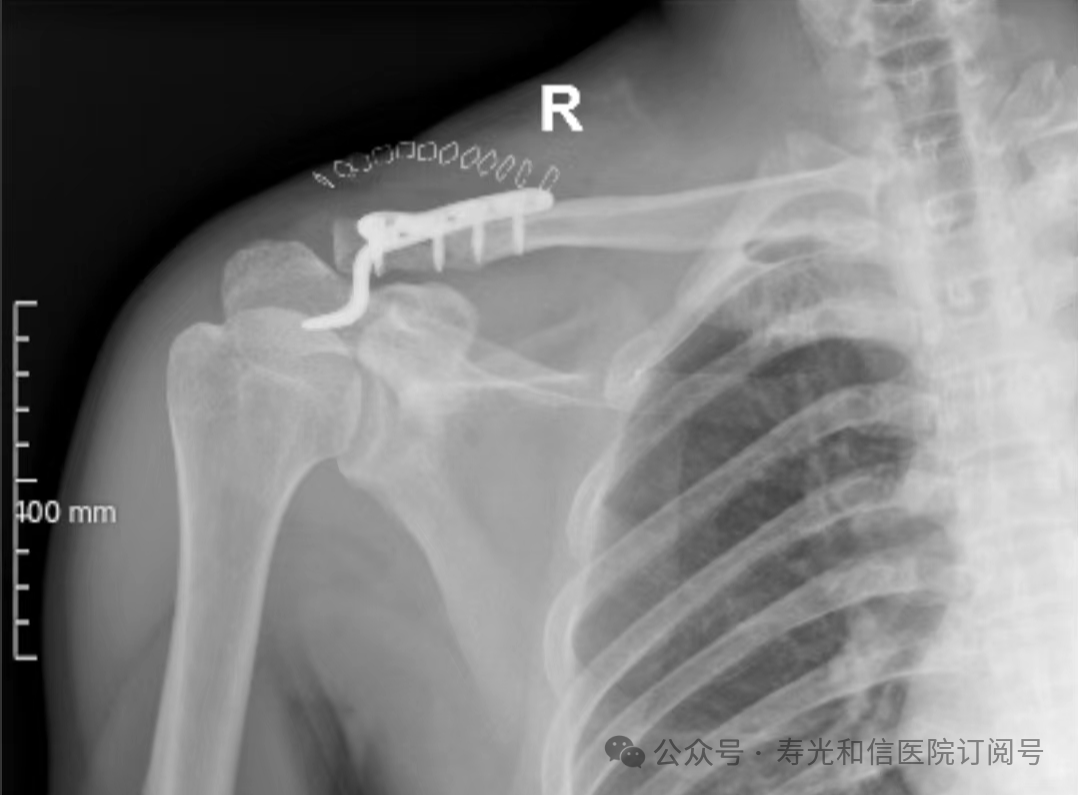

患者经120接诊,完善相关辅助检查后收入寿光和信医院骨外科。检查发现,患者右锁骨骨折、左股骨颈骨折、左大转子撕脱骨折、右膝关节前交叉韧带止点撕脱骨折、右膝关节外侧副韧带损伤、颅骨骨折及全身多处皮肤挫伤。因患者是外地来寿人员,家属短时间内不能赶过来,并且患者家庭经济条件较差,没有缴纳住院手术费的能力。但是股骨颈骨折后,股骨头坏死发生几率较高,手术越早进行,越有利于减少发生股骨头坏死的几率。骨外科主任李刚始终牢记救死扶伤的神圣职责,本着为病人负责的原则,坚定地选择先行为患者实行手术治疗。

与患者本人充分沟通后,李刚主任率领骨外科团队,经过充分的术前讨论及术前准备,于2024年9月1日为患者在全身麻醉下实施了4个半小时的内固定手术治疗。“时间就是生命”,手术过程中,全体参与人员密切观察病情变化,敏锐发现早期异常指标,争分夺秒,一丝不苟地做好各项抢救救治工作,做到瞬间判断、正确评估、果断处理,赢得了抢救患者的“黄金时机”,确保了手术的顺利完成。

在为其进行股骨颈骨折治疗时,手术团队为其采取了股骨颈动力交叉钉系统,这是一种新型股骨颈内固定系统,属微创植入,较从前的技术具有手术时间短、创伤小、力学稳定、滑动加压等优点。同时,患者恢复快,可早期离床、不负重下活动,缩短住院时间及康复时间,有效降低患者股骨颈骨折不愈合发生率,降低长期卧床合并症和死亡率。